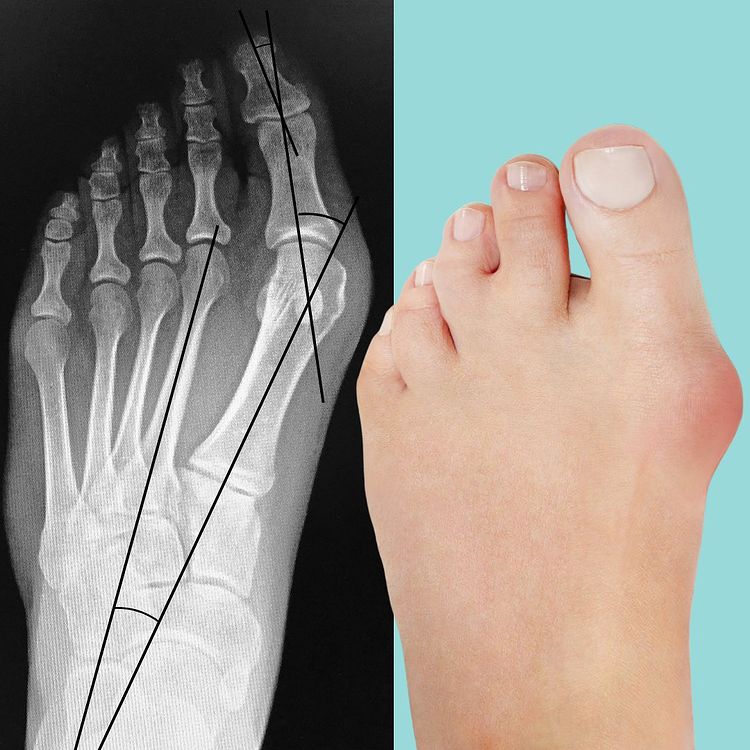

• Joanetes, fascite plantar e dedos em garras